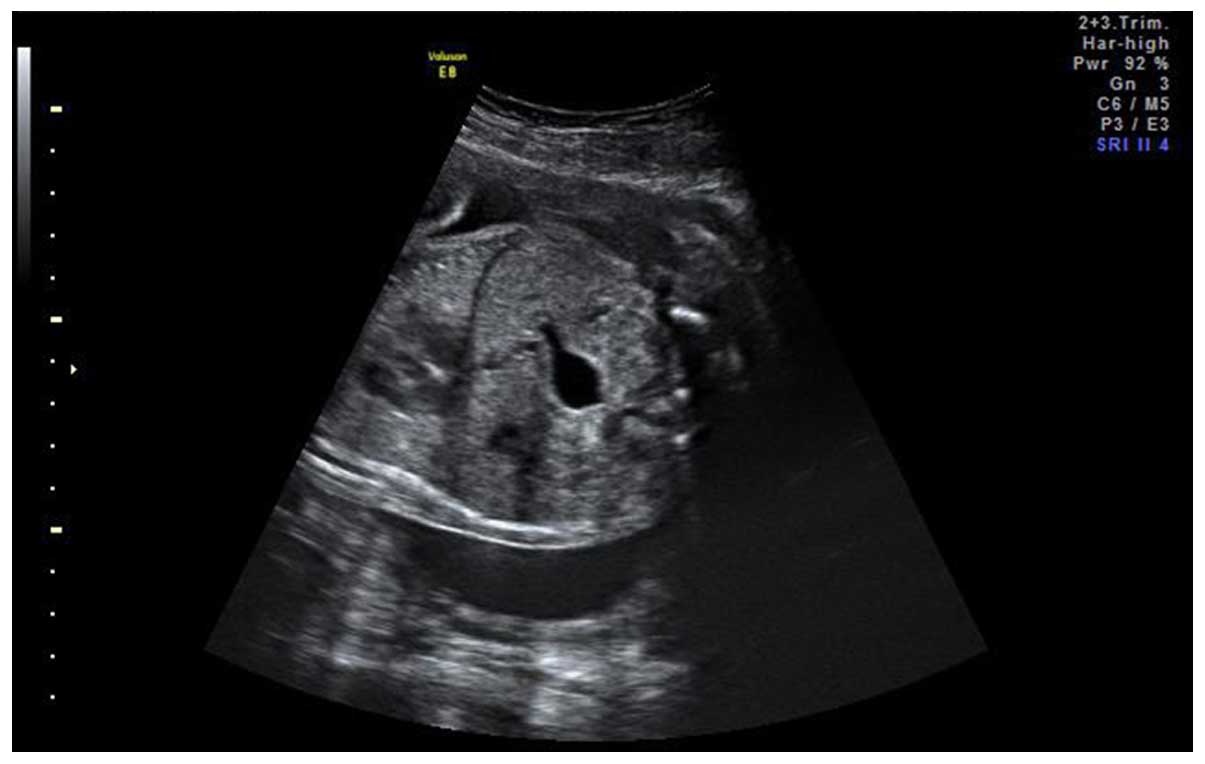

Fetal Brain Cyst Ultrasound

Intracranial cysts are central nervous system malformations involving different brain regions, and commonly diagnosed during prenatal period. Fetal choroid plexus cysts (cpc) are often detected on prenatal ultrasounds and pose a need to formulate protocol for management and. It’s estimated that choroid plexus.